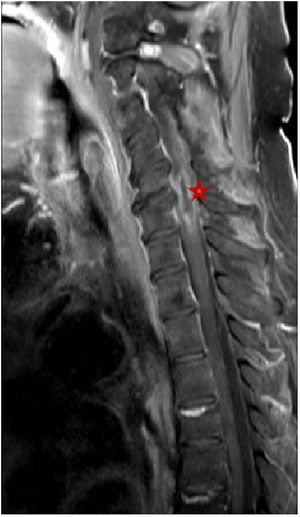

Pasados dos meses del último ingreso, acudió a urgencias por radiculopatía refractaria a analgesia convencional y pérdida de fuerza en miembros inferiores, destacando a la exploración paresia flácida de ambos miembros inferiores (0/5) y del miembro superior derecho (2/5). La resonancia magnética reveló múltiples lesiones ocupantes de espacio (12 en total) en territorio infra y supratentorial (fig. 1), así como un absceso intramedular a nivel C5–C6 (fig. 2).